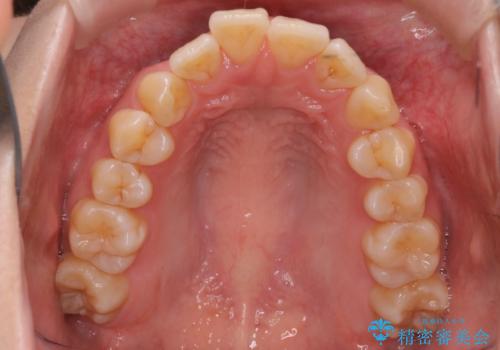

- 前歯が出ていることと、下の歯のがたがたで歯磨きがしにくいことを主訴に来院されました。

マウスピース矯正の希望があり、ワイヤーリカバリの可能性を伝えたうえでインビザライン抜歯矯正を行っています。

来院が途中途絶えたこともあり、4年ぐらい期間がかかりましたが、インビザラインだけで治療を終えることができました。